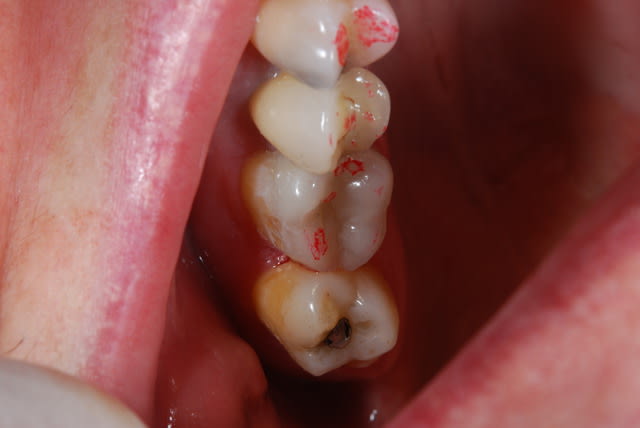

Oune plous pitite ...)))

La 16 est magnifique , le compo de la 4 également (le pan d'émail sert de point de contact , youpi)...

Patient habituel si on peut dire , pris en paro par ma femme , reparti chez un ami...à lui pour les prothèses , reviendu chez moi .

J'ai des bourrages , effectivement c'est ballot et à part refaire les cérams , je ne vois pas .

Pis chuis nul en composite , on va faire un onlay , c'est la seule soluce . Oui je vais en profiter parce que d'ici 2 ans je serai à la retraite , et la moutouelle...là on me rembourse tout . Je vais quand vous faire un devis à tout hasard...)))